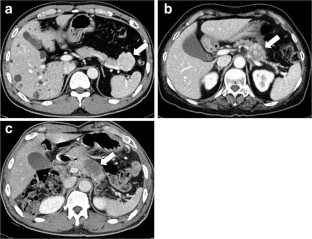

Fig. 2